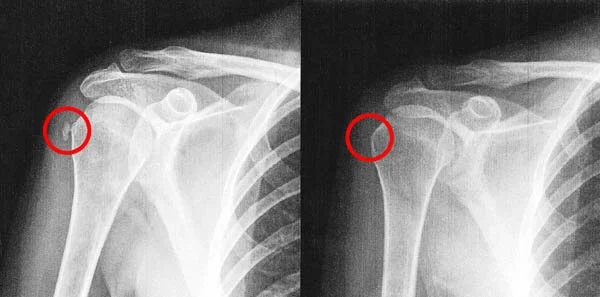

I kept my four week follow-up appointment with the orthopedic group so that I could let them know how well I had progressed. I confessed to him that I stopped all medications the day after I saw him and that I never went to physical therapy. I explained that it was not due to me trying to be a bad patient, but only because I didn’t have painful symptoms any longer. The physician was happy that I had such great success and it didn’t matter to him how I did it as long as it worked. But, before I left, I asked him if we could do an x-ray to see what became of the calcification. He assured me that it would still be there. He warned against radiating me if he didn’t have to, but I asked for just one view and he agreed. When he showed me the x-ray he was speechless, he couldn’t believe that the calcium deposit on my initial x-ray had melted away.

UPDATE: Carmela provided the office with the famous X-rays that stumped her orthopedic physician!